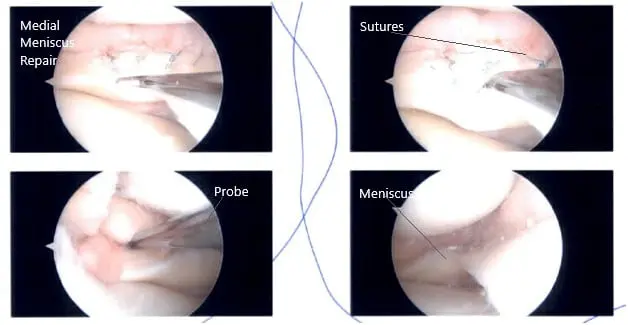

A lateral entry portal was established, and the knee joint was examined. A peripheral tear of the medial meniscus was found. A grade 1 to grade 2 osteochondral lesion of the medial condyle of the femur was also found. The ACL had some fraying and degeneration.

There was no lesion on the meniscus or lateral femur and condyle. The patellofemoral joint was inspected and found to be good. Now, the repair of the medial meniscus was performed. FasT-Fix sutures were used. Seven sutures were used to fix the peripheral tear from the posterior horn to the midbody.

Gross fixation and stability of the meniscus was found to be satisfactory. Final arthroscopic pictures were taken. The knee was lavaged with copious normal saline. The wound was closed